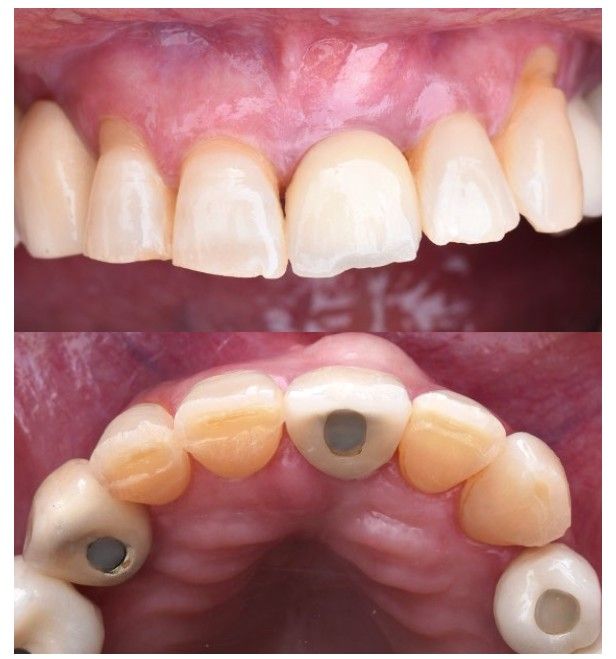

Tras la colocación del implante, se instaló un pilar transepitelial Klockner® tipo Permanent, recto unitario NV de 2 mm de altura, atornillado con un torque de 30 N/cm. Posteriormente, mediante un casquillo provisional de titanio atornillado, se llevó a cabo la recaptura de la corona provisional tipo “cáscara de huevo” previamente confeccionada por el laboratorio (Figura 7). Para ello, se empleó acrílico autopolimerizable (TAB 2000, Kerr®), seguido de la aplicación de composite fluido (Tetric EvoFlow® A2, Ivoclar Vivadent®) para la conformación progresiva del perfil de emergencia, garantizando un adecuado ajuste, acabado y pulido de la restauración provisional (Figura 8 y 9). Dado que las cargas oclusales resultan desfavorables en este tipo de casos, se redujeron los contactos en máxima intercuspidación y durante los movimientos excursivos en el provisional de carga inmediata, con el objetivo de minimizar los micromovimientos y preservar el éxito del tratamiento. La paciente acudió a revisión a los 15 días para retirada de sutura, sin registrar complicaciones en este periodo de tiempo (Figura 10).

El implante se mantuvo en fase provisional durante un periodo aproximado de cuatro meses desde su colocación. Tras esta fase de provisionalización, se realizó la toma de impresión analógica mediante un coping de impresión personalizado, diseñado para reproducir de forma precisa el perfil de emergencia previamente modelado con la restauración provisional (Figuras 11 y 12). A partir de estos registros, se confeccionó e instaló la corona definitiva atornillada, con una oclusión suavizada para evitar sobrecargas del implante (2.1i). La imagen clínica (Figuras 13 y 14) y el CBCT postoperatorio (Figura 15) evidencian una situación clínica y radiológica favorable, con estabilidad de los tejidos periimplantarios a los cuatro años de seguimiento.